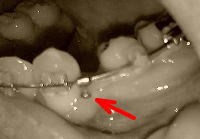

上顎、今回でちょうど1年目になりました!隙間もすっかりなくなって(´・ω・`) 、もうこの出っ歯どうしてくれよう、という感じですが、とりあえず、調整から。上顎の隙間を埋めるためについていたパワーチェーンが外されました。これで、上顎は一旦終了とのこと。 Σ(゚Д゚)ところが、先生から驚きの一言が。「噛み合わせを合わせるには、上の歯を削ったほうがいいかもしれない」上の歯のサイズが大きすぎるとのことなんですね。「ちょっとね、見た目も、1番は下の歯とのバランスからすると、ちょっと大きいんですね」そうなんです。それは私も激しく感じていました。「1番だけじゃなくて、2番もデカいですよね?」と言うと、「そうですね、大きいです。えーとね、3番も、5番ぐらいまでね、大きめですね」と、ちょっと言いにくそうでしたが、とにかくデカいと。受け口だった下顎は順調に下がっているので、できれば上の歯はそれに合わせてもうすこし引っ込めたい。そうなると、削るしか方法はないとのことで、私は答えましたね。「思う存分削ってくださいw」削るのは下顎が終了してから、ということで、下顎の調整に入ります。下顎の右側の抜歯痕、あと0.5ミリといったところまで狭くなりました(画像赤矢印)。さらに狭めるべく、引き続きパワーチェーンで3番←→6番を引っ張っています。そして、未だに左上3番と当たってうまく噛めない左下3番をどうするか、という話になりました。先生は上3番の内側を削ったら、と仰いましたが、私はちょうどこの歯が外側にちょっとだけはみ出てねじれているのが気になっていたので、それを言ってみました。すると先生は「なるほど。そうですね。じゃあそこを改善してみましょう」と。言ってみるもんだv処置としては、3番のブラケット付け直しで内側に入るようにする、捻れを取るためにブラケットとワイヤーがゴム留めになりました。ゴム掛けは引き続き、右側は上6番←→下3番、左側は上3番←→6番です。このピンクの部分、これで引っ込んでくれるかな?正面・先月今日